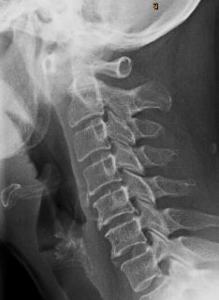

Near Normal Spine

This side-view X-ray shows what we call a "near normal" cervical spine. The patient is facing to the right, allowing us to view the natural forward curve of the neck, which acts as a shock absorber. The disc spaces between C2 and C7 appear thick and even, and the vertebral bodies have clean, square shapes with well-defined borders — all indicators of a healthy spine.

When subluxations occur and remain uncorrected, predictable patterns of degeneration begin. These changes affect spinal structure, nerve function and overall health, gradually progressing into more advanced phases.